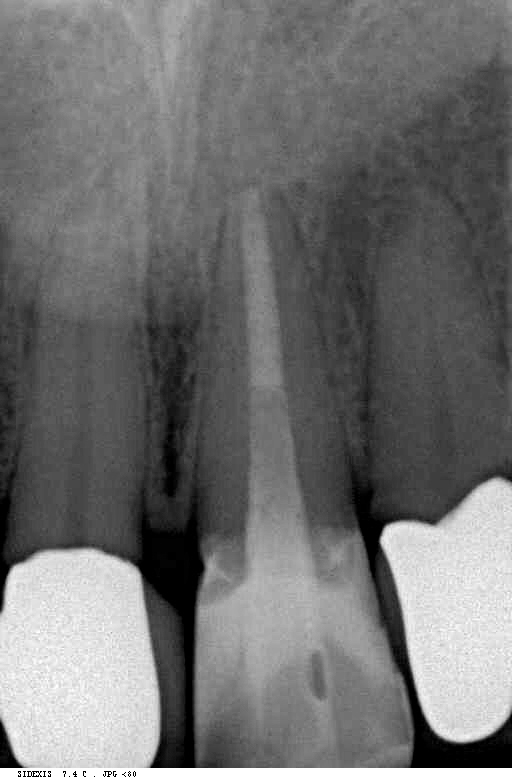

Kompositaufbau epigingival Veröffentlicht 16. März 2012 am 512 × 780 in Erzeugung eines Ferruleeffektes durch Extrusion eines Frontzahnes postendodontisch